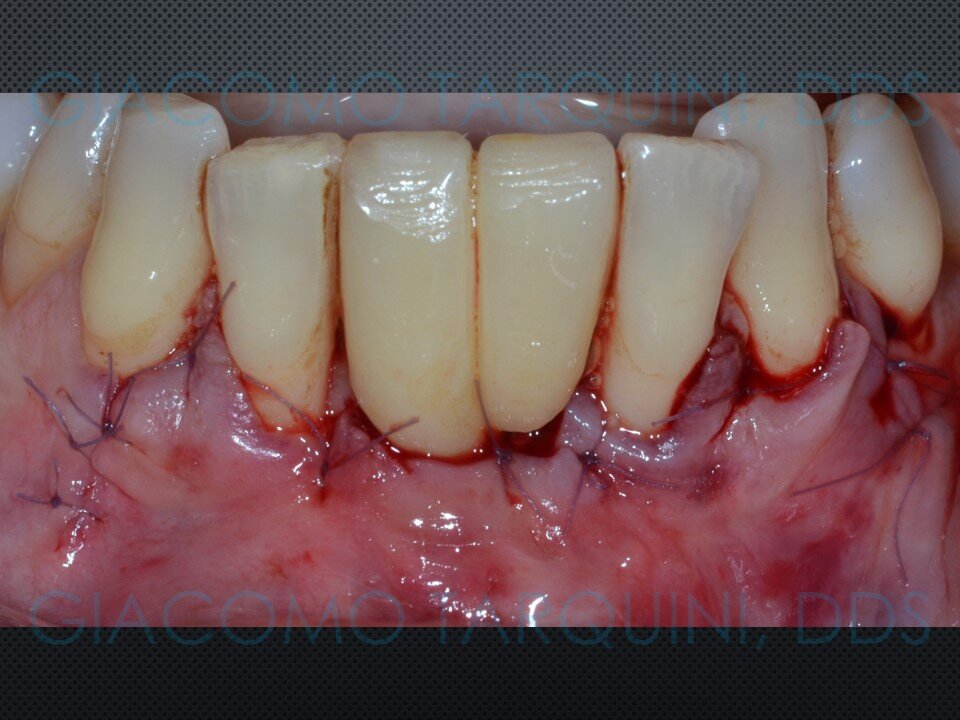

Viene presentato un caso di rigenerazione ossea guidata attorno a un impianto che aveva perso parte del suo supporto osseo a causa di una pregressa peri-implantite. Le spire esposte vengono decontaminate sfruttando le note proprietà della cavitazione ultrasonica per mezzo del dispositivo “Piezoclean by Dr. Giacomo Tarquini”, mentre la fase rigenerativa viene effettuata secondo il protocollo denominato “Poncho technique”. Questo approccio consente una ricostruzione prevedibile del tessuto osseo senza dover necessariamente rimuovere l'abutment e la protesi al fine di ottenere una guarigione sommersa.

In casi selezionati, questa tecnica permette di mantenere estetica e funzione della riabilitazione protesica su impianti, riducendo al contempo sia l’invasività dell’intervento sia i tempi complessivi della riabilitazione, poiché elimina completamente la necessità di rimuovere e successivamente reinserire sia la corona protesica sia l’abutment.

- Sutura dei lembi in accordo con la tecnica selezionata

La decontaminazione della superficie implantare con il dispositivo “Piezoclean by Dr. Giacomo Tarquini”, combinata con il protocollo noto come “Poncho technique”, consente una ricostruzione prevedibile del tessuto osseo attorno a un impianto affetto da perimplantite. Questo approccio comporta una significativa semplificazione delle fasi chirurgiche e una bassa morbidità operatoria, riducendo al contempo in modo sostanziale i tempi complessivi della riabilitazione.